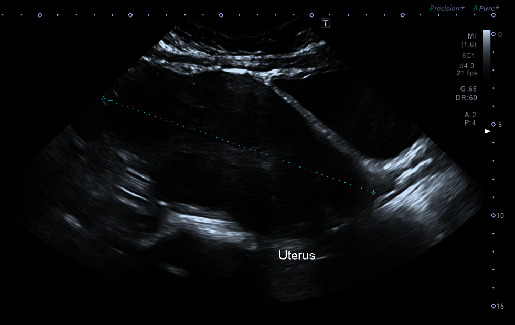

Introduction: Uterine leiomyomas are a frequent finding in women of reproductive age. However, rare, unusual growth patterns exist, such as atypical, cellular, mitotically active, myxoid, and epithelioid leiomyomas, and present a major concern as they mimic highly malignant uterine tumors such as uterine leiomyosarcomas. An example of such cases is the epithelial type leiomyoma which is the subject of our report in a 35-year-old female. Case: A 35-year-old, nulliparous lady presented with abnormal uterine bleeding to the emergency department. Workup revealed a suspicious uterine mass that was extending from the intramural part of the fundus down the cervical os. The patient was managed by open myomectomy without complications. The final pathology report revealed an extremely rare benign epithelial type leiomyoma, no malignancy, areas with minimal atypia and low mitotic activity (< 5/10 high power fields), and areas of focal necroses (possibly ischemic type) were seen. No coagulative tumor necrosis was noted. Conclusion: Uterine leiomyomas are a common pathology of the uterus that can be confused with malignant tumors, especially in the setting of unusual growth patterns such as the epitheloid leiomyomas. Definitive management involves myomectomies with regular follow-up with favourable prognosis. It is important to properly manage these cases to avoid the overdiagnosis and mistreatment not to mention the repercussion of false diagnoses on the patient's mental health and well-being.